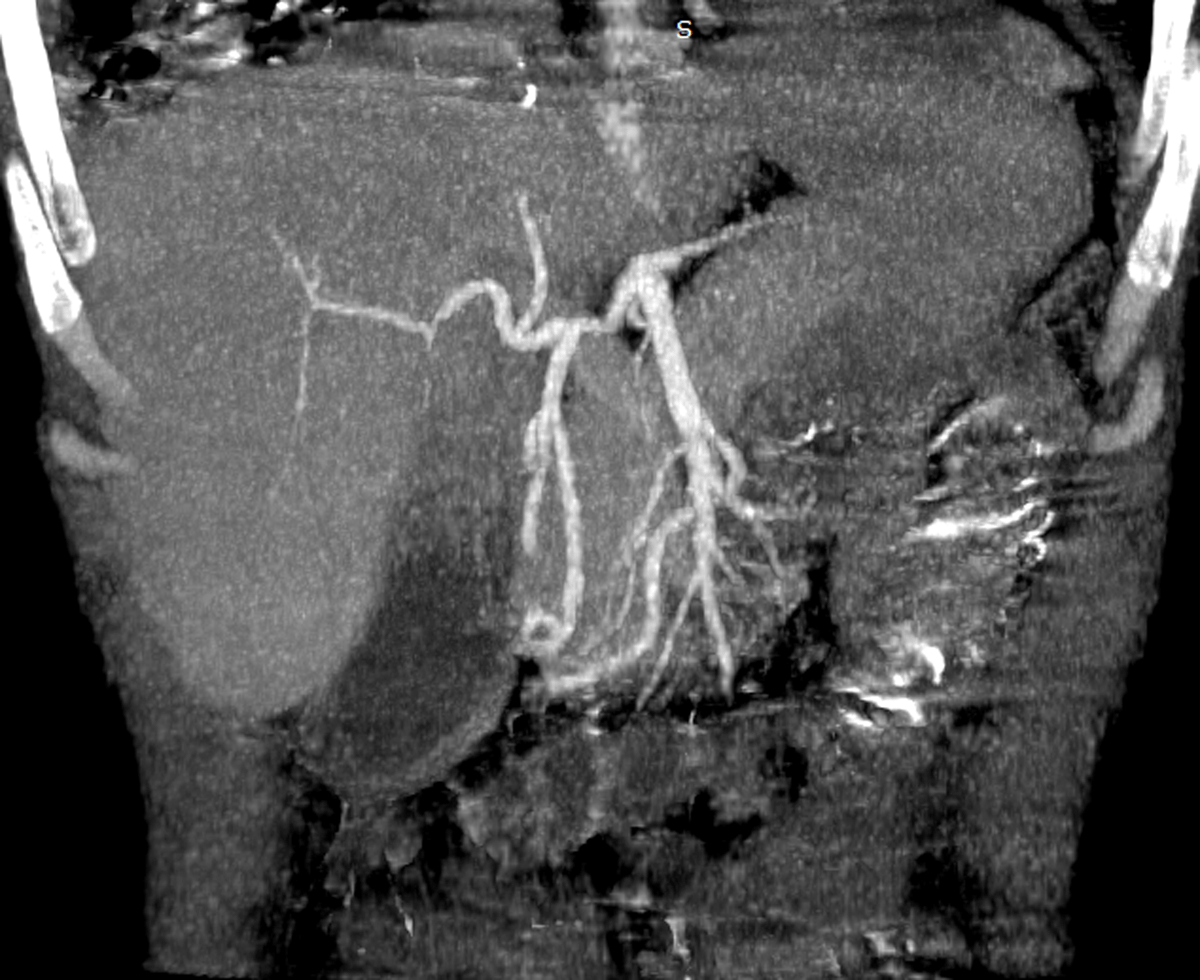

A contrast-enhanced abdominal computed tomography was performed. Axial images of portal phase demonstrated multiple wedge-shaped non-enhancing areas at the periphery of the spleen suggestive of splenic infarcts (Figure 1a). Splenic vein was permeable (Figure 1b). Axial and sagittal images of arterial phase revealed a small splenic artery related to severe stenosis and angulation of celiac axis caused by a thick soft tissue band (5 mm) anterior to the abdominal aorta creating a hooked appearance (Figure 2a, b). Coronal maximum intensity projection CT showed a prominent gastroduodenal artery with large collateral vessels around the pancreatic head (Figure 3). Median arcuate ligament syndrome causing splenic infarcts was retained and the patient was referred to vascular surgery service.

Figure 3